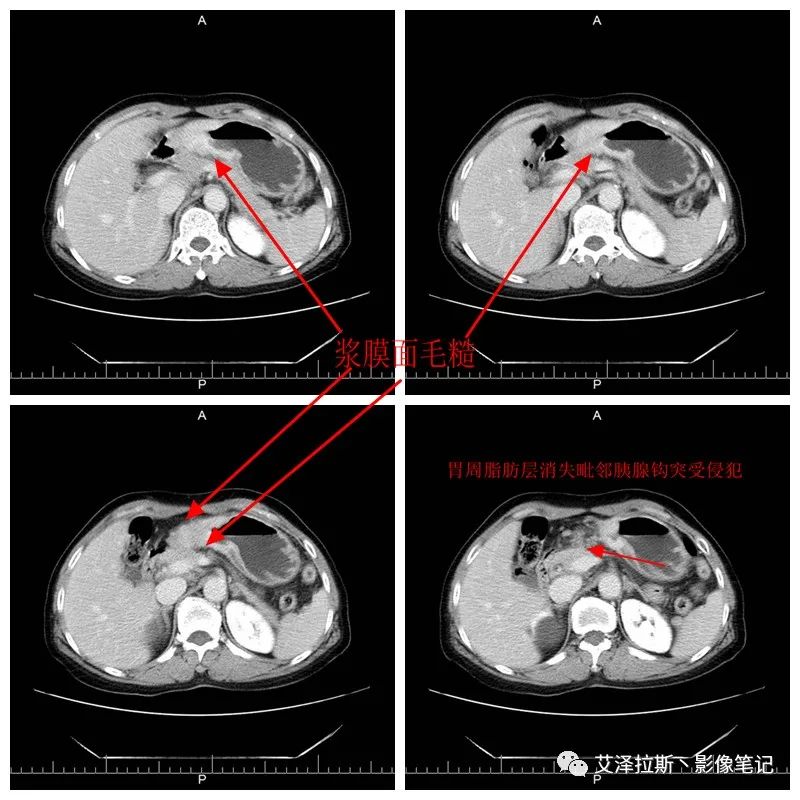

【影像所見】 胃竇部狹窄,胃壁環(huán)形增厚,小彎側(cè)見一巨大潰瘍,周圍伴“環(huán)堤征”,漿膜面不完整,胃周脂肪見網(wǎng)格狀條索影,病灶與肝臟左葉、胰腺鉤突脂肪間隙消失,增強(qiáng)掃描病灶明顯強(qiáng)化。引流區(qū)內(nèi)約15個區(qū)域淋巴結(jié)受累。

【診斷意見】 胃竇部胃癌(T4N3期) 該病例腫塊突破漿膜層,與肝臟左葉、胰腺鉤突分界不清,脂肪界面消失,定為T4期; 受累及的淋巴結(jié)為15個區(qū)域,定為N3; 有無遠(yuǎn)處轉(zhuǎn)移尚不明確,所以M期暫時無法確定。